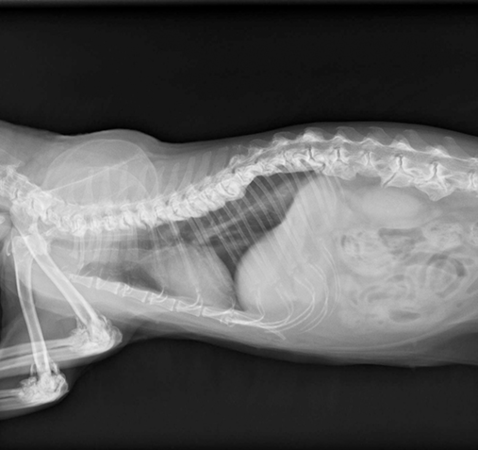

▲園寶X光顯示有骨刺的情況。(圖/慈愛動物醫院提供)

台中蘇格蘭摺耳貓「園寶」曾是家裡的「小跳躍王」,卻在這半年變得幾乎不願移動、不喜歡被抱,甚至走路時步伐也顯得小心翼翼。經獸醫檢查後,才發現牠的脊椎多處長出了骨刺。在獸醫師的建議下,飼主讓牠嘗試外泌體再生療法,沒想到又能看到園寶邊抓貓抓板、邊呼嚕的可愛模樣。

慈愛動物醫院獸醫師表示,很多飼主誤以為貓不動是「懶」或「老了」,其實可能是關節、骨骼問題,尤其摺耳貓這類品種機率較高,「骨刺雖然小,卻會造成摩擦壓迫,讓毛孩不自覺出現慢性疼痛」。